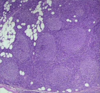

What does this indicate?

This is reactive follicular hyperplasia. Note the sharp polarized mantle and “starry sky” appearance due to tingible body macrophages in the center of the lymph node gobbling up cells turning over in the germinal center.